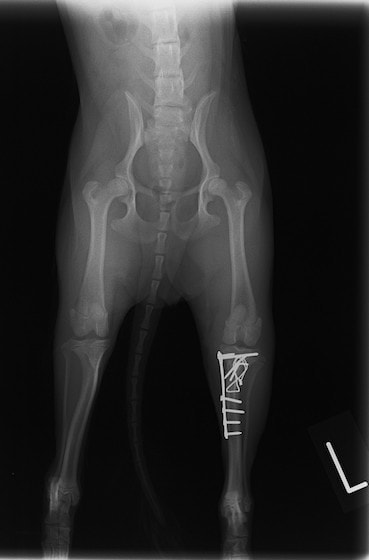

骨盤骨折 : 症例1 | 症例2 | 症例3 | 症例4

脛骨骨折 : 症例1 | 症例2 | 症例3 | 症例4 | 症例5